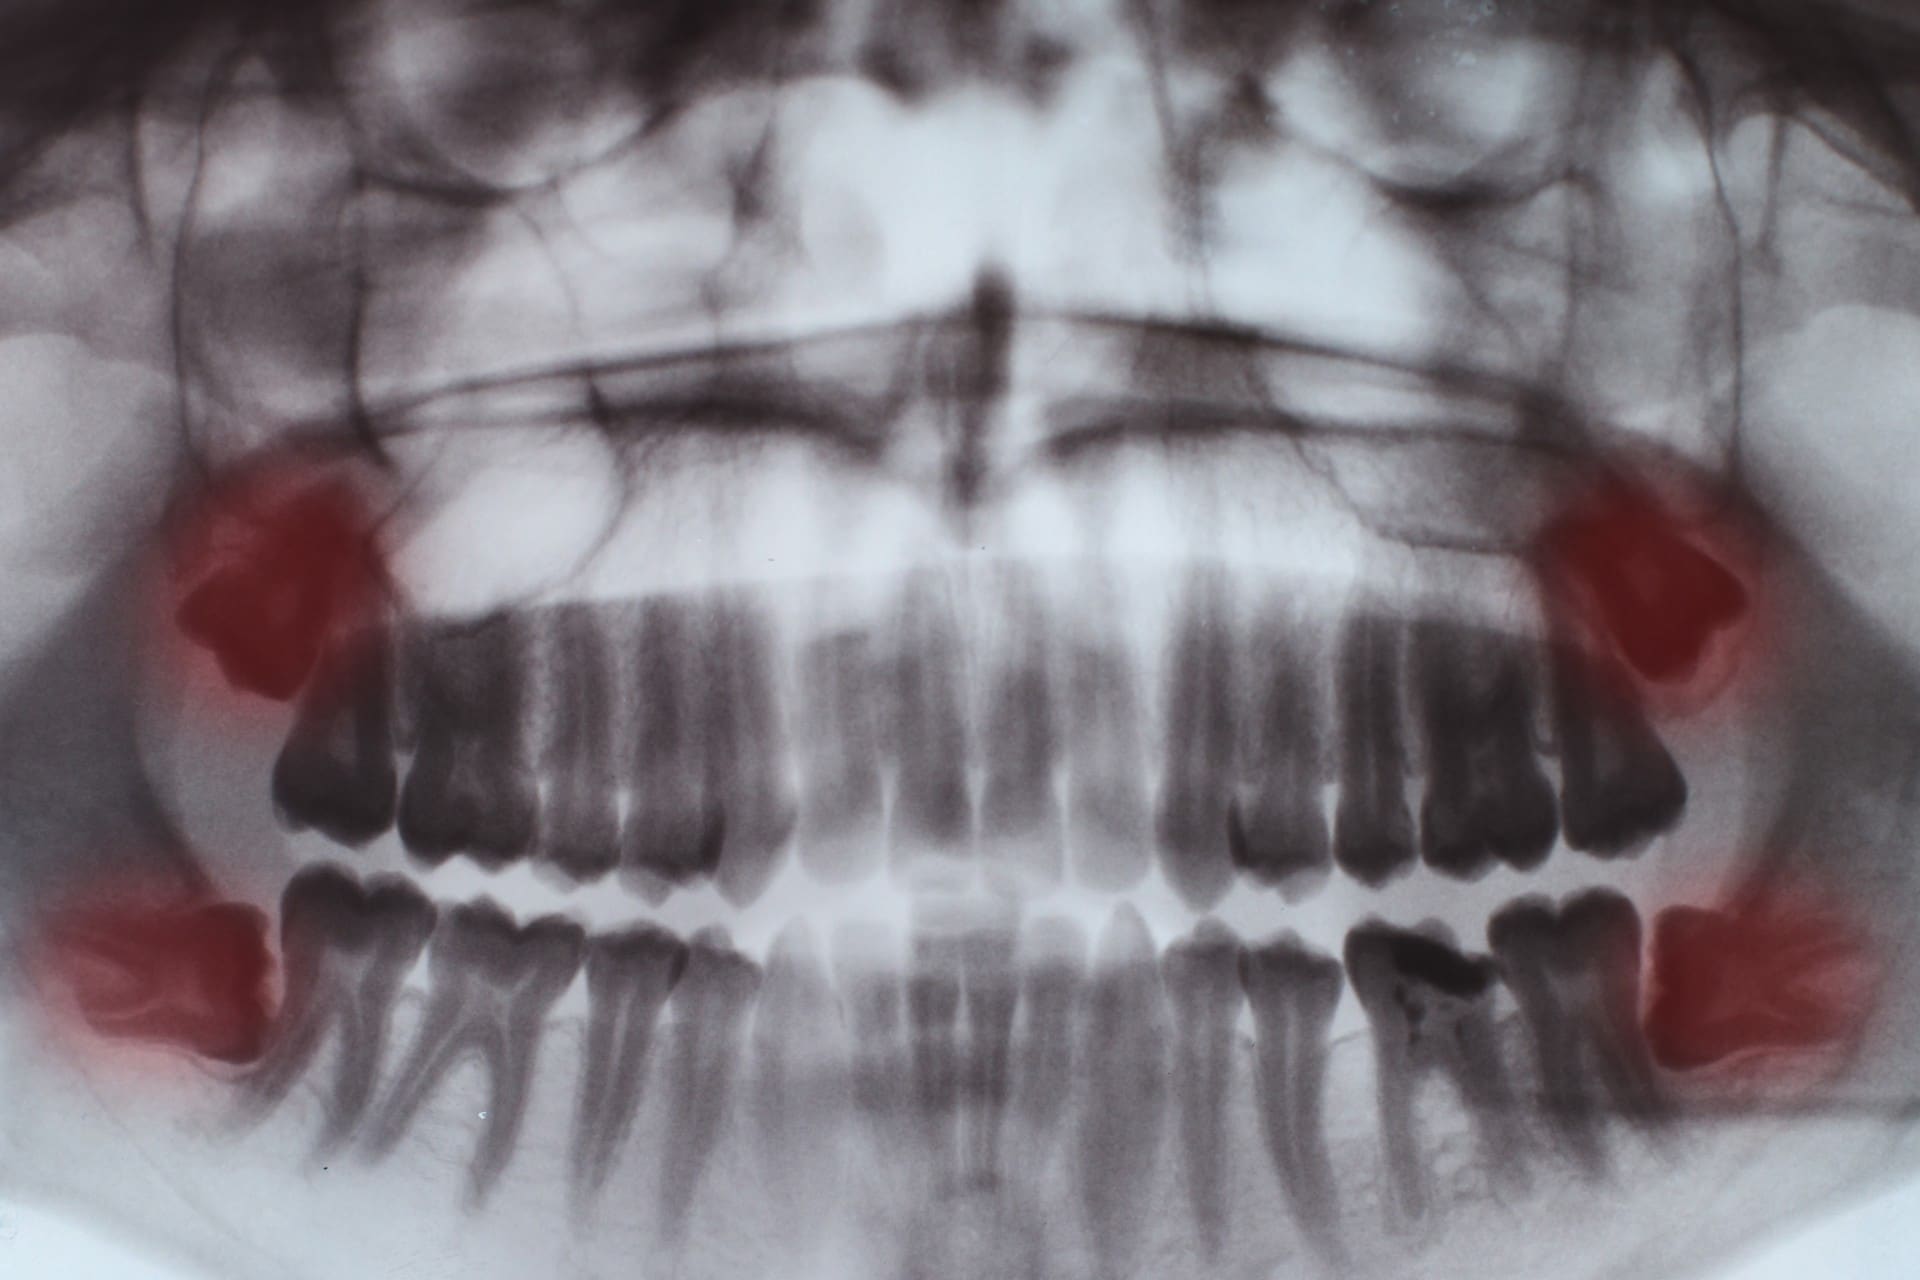

Impacted tooth (tooth impaction) Studio Dentaire

From www.studiodentaire.com

Impacted tooth (tooth impaction) Studio Dentaire What Is An Impacted Wisdom Tooth This can lead to a number of oral health problems, including infection,. These teeth typically come in during the late teen years or early adulthood. Impacted wisdom teeth happen when your third molars become partially or fully trapped in your gums or jawbone. Wisdom teeth are the third set of molars in the very back of your mouth. Impacted wisdom. What Is An Impacted Wisdom Tooth.